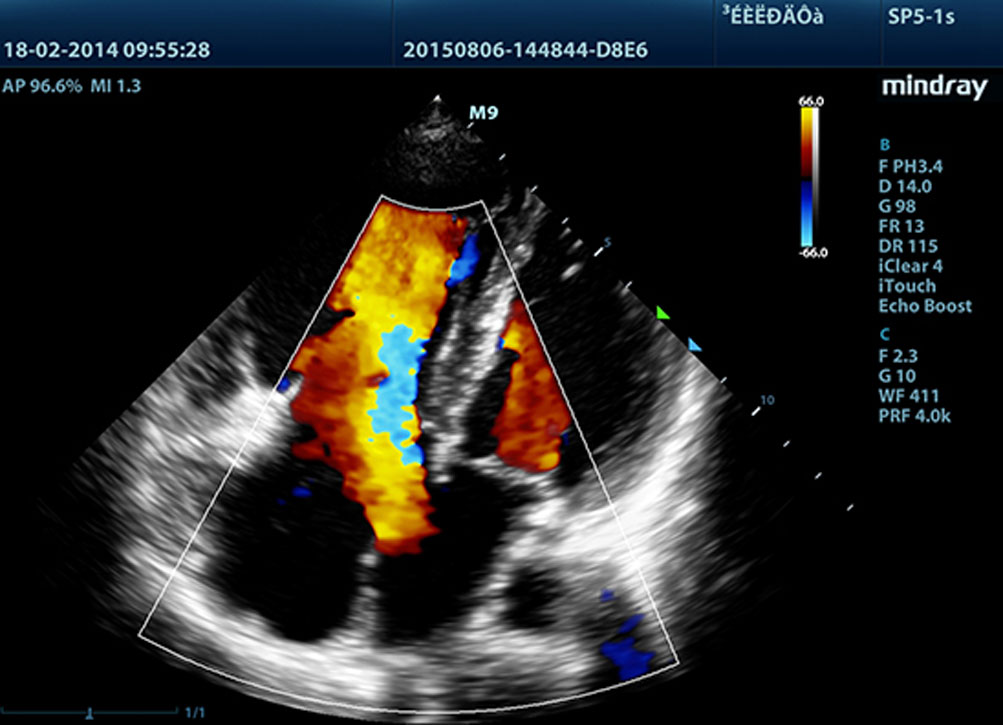

• TDI

С помощью тканевой доплеровской визуализации можно определять количественные показатели движения и функционирования сердечной мышцы, используя режимы полной визуализации для быстрой и непосредственной диагностики.

• ЛВК со стресс-эхокардиографией

Функциональность премиум-класса позволяет системе выполнять контрастирование ЛЖ во время стресс-ЭхоКГ, улучшая разграничение между тканями миокарда и депо крови и обеспечивая лучшую визуализацию поверхности эндокарда.

Ультразвуковая диагностическая система М9 сочетает в себе оптимальную функциональность премиум-класса и мобильность. Основываясь на ультразвуковой платформе нового поколения mQuadro от компании Mindray, портативная система выводит отраслевые стандарты на новый уровень. Модернизированные процессоры приема и передачи сигналов обеспечивают высокую чувствительность и точность обнаружения эхо-сигналов. Благодаря инновационным технологиям, использованным при производстве датчиков, достигается более высокая проникающая способность и улучшается пространственное разрешение, что позволит вам осуществлять высококачественную диагностику.